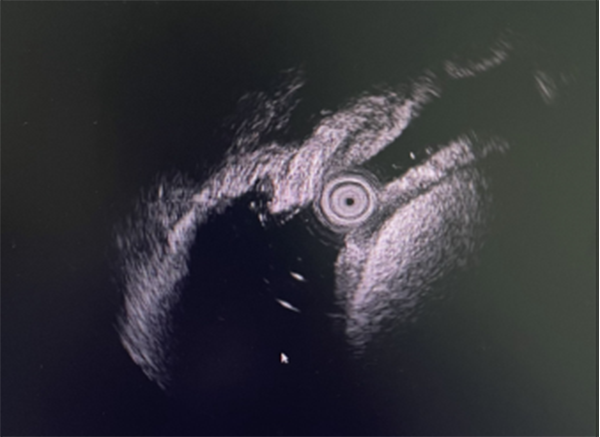

航空总医院消化病中心接诊后仔细询问查体,行便常规检查有便潜血免疫法阳性,通过电子肠镜检查时在横结肠处见一巨大粘膜下隆起凸入肠腔,表面有充血糜烂,肠腔近乎被肿物完全堵塞。超声内镜(EUS)显示横结肠黏膜下层巨大高回声肿物,脂肪瘤可能(图1)。CT检查提示横结肠巨大粘膜下肿物,约6.7cm×4.3cm,近似人体拳头大小,几乎占据整个肠腔(图2)。

图1.EUS显示横结肠巨大病变呈黏膜下均匀高回声改变。